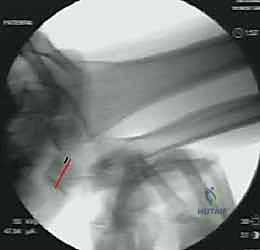

C. Creating the Ulnar Head Tunnel

1. Identifying Drill Site: "Back to the dorsal wrist. We need to create a bone tunnel through the ulnar head." Identify the ulnar head. The drill entry point is typically on the dorsal aspect of the ulnar head, just distal to the articular cartilage.

Image

TECH FIG 2D • A tunnel is drilled in the ulnar head.

1. Drilling the Tunnel: "I'll take a 2.5 mm drill bit, please." Drill a unicortical tunnel through the ulnar head, aiming towards the fovea, or slightly volar and distal to exit on the ulnar styloid or fovea region. The exact trajectory is crucial to mimic the ulnocarpal ligament's course.

TECH FIG 2E • The tendon graft is passed through the ulnar head.

> **Surgical Warning:** Drill under constant fluoroscopic guidance to confirm trajectory and prevent iatrogenic fracture of the ulnar head or damage to the articular surface. Ensure the tunnel is smooth and free of sharp edges that could fray the graft. Use a Kirschner wire to create the pilot hole, then over-drill if necessary.